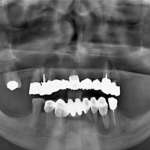

Riabilitazione mandibolare a carico immediato con sistema Trefoil. Caso clinico con follow up a... Premium

Attraverso la descrizione di un caso clinico, viene presentata una tecnica che consente di realizzare una riabilitazione fissa mandibolare su tre impianti mediante l’uso di guide chirurgiche prefabbricate e una barra prefresata in titanio.